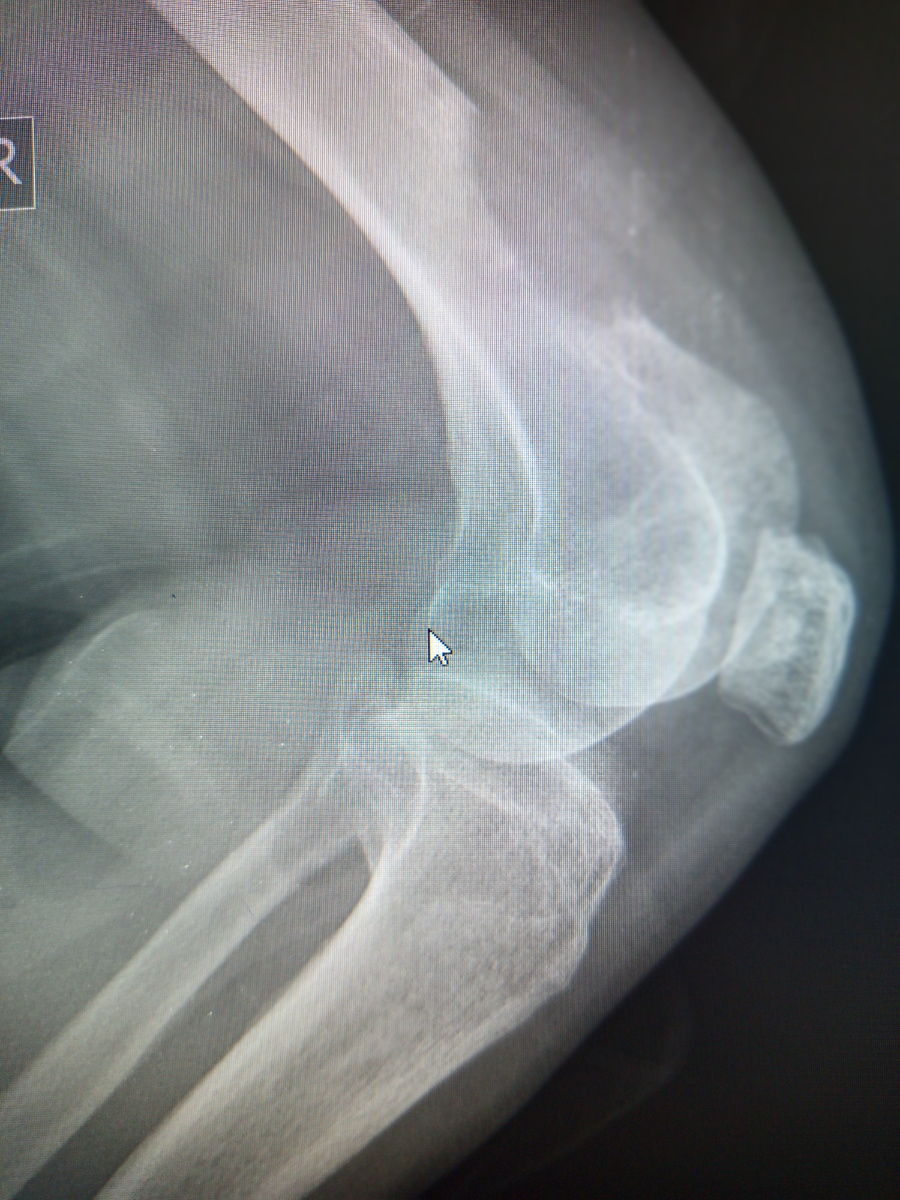

–Пока не знаю, упала , колено болит.

Ладно , завезла.

Сделала снимок коленного сустава.

–Нет , там у вас пол кости над коленом.

Читаю заключение МСКТ:MTS нижней трети бедренной кости.

Понятно , так и укажем.

Бедная женщина 39 лет всего , но онко не жалеет никого.